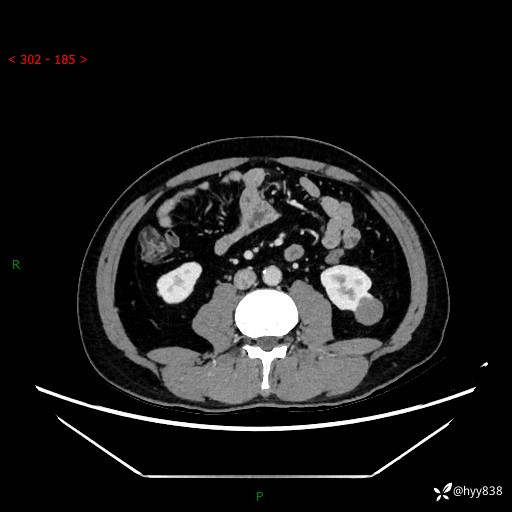

中年男性,左侧腰背部间断性胀痛不适。第一眼“乳头或囊肿”,有无意外---(有结果)

【患者信息】:41岁/男

【主诉】:左侧腰背部间断性胀痛不适1周

【现病史及既往史】:患者1周前无明显诱因出现左侧腰部疼痛,呈间断性胀痛,休息后可缓解,无放射痛,偶可见肉眼血尿,无血块,无尿频尿急尿痛,无夜尿增多,无畏寒发热、咳嗽咳痰等症状。于我院查双肾CT示:左肾占位性病变,左肾下极囊性病变,左肾轻度积水,胆囊多发结石。今为求进一步诊治来我院,门诊以“左肾占位性病变”收治入院。 起病以来,患者精神佳,饮食、睡眠良好,大便正常,小便如上诉,体力体重无明显变化。

【检查】:肾脏CT平扫+增强